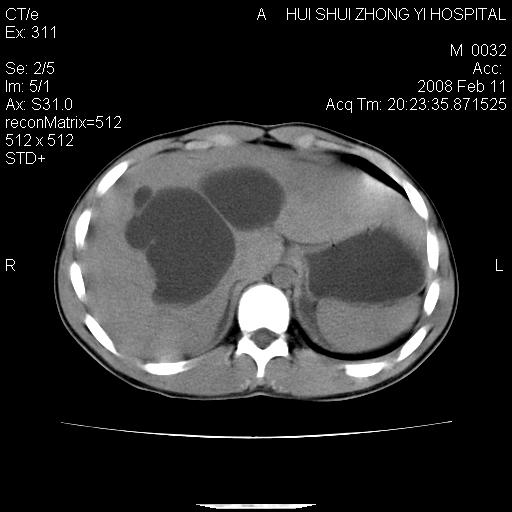

标题: CT11660:男,16岁,现腹痛剧烈,现发烧、头痛、恶心呕吐 [打印本页]

标题: CT11660:男,16岁,现腹痛剧烈,现发烧、头痛、恶心呕吐

8年前曾在贵洲省人民医院b超诊断为肝内胆管结石。现腹痛剧烈,现发烧、头痛、恶心呕吐县医院b超示胆囊肿大大小159*46mm,囊内见6*5mm强回声光团,胆各总管内径56mm。提示:胆囊结石、急性胆囊炎、胆总管重度扩张。

胆囊结石.急性胆囊炎.重度胆管扩张.右侧胸腔少量积液,建议ct增强

考虑先天性胆管囊肿;胆囊增大并结石。右侧胸腔少量积液,建议ct增强。

caroli囊肿并囊内结石。胆囊增大并胆结石。典型!

先天性胆管囊肿,胆囊结石、胆囊增大,右侧少量胸腔积液。